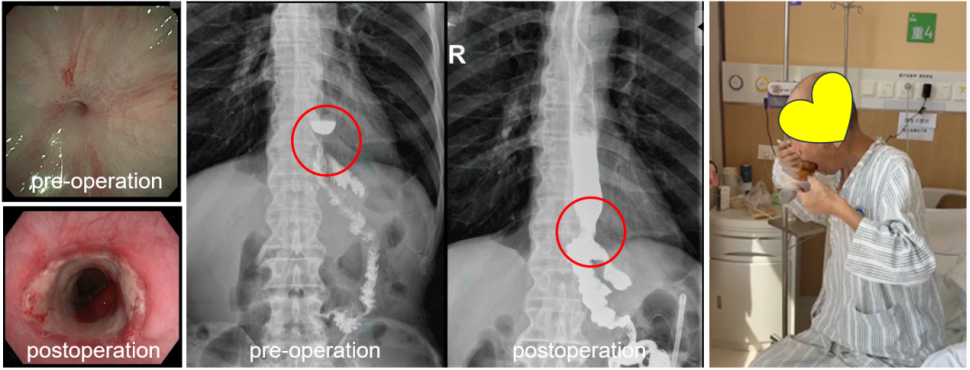

3月12日早上刚到病房,严小鹏医生就匆匆递给我几张胃镜和食管造影的报告单,同时,我看到旁边凳子上坐着一名极度瘦弱的老人,我意识到这又是一个奔着磁外科技术而来的复杂病患。贲门胃底恶性肿瘤术后食管空肠吻合口重度狭窄,外院内镜下球囊扩张无效,患者近3个月未进食、进水,并且随手都带着一个纸杯子,重度的食管狭窄让他连唾液也无法下咽。这个病患的治疗将极其复杂,并且风险很高,一时间我竟然不知如何着手。我缓缓抬头看向严小鹏医生眉头微蹙的脸,一双坚定而深邃的眼神让我意识到这名患者应该是有希望的。

在进修期间能够亲历磁外科技术治疗复杂临床疾病将是我莫大的荣幸。在接下来的时间里,严小鹏医生带着我亲自给患者进一步完成了食管造影和胃镜检查,最终,我们在3月18日给患者实施了开腹联合胃镜下食管空肠吻合口狭窄磁力再通术。这个手术需要多个科室不同专业的医生共同参与完成,除肝胆外科磁外科团队的严小鹏医生、师建华医生、王荣峰医生、张苗苗医生外,还有腹部外科的张雷医生、卢强医生,消化内镜的任晓阳医生、刘鑫护士,麻醉手术部的毕阳医生、刘洋护士和林晓伟护士,还有影像科术中拍片人员的参与帮忙(这是后来我向严小鹏医生索要的参与人员,我希望能记住他们)。一个需要这么多医护人员和科室共同参与配合的手术,在严小鹏医生的协调指挥下却显得不慌不乱、井井有条,我想这应该是他们经过好多例磁外科手术后磨练出来的默契。另一方面我也深深地感受到西安交通大学第一附属医院医生们不嫌麻烦、不畏艰难、一心只为救治患者的高尚品质。

3月30日(患者术后12天)在去医院的地铁上,我还一直在想这个病人的磁体什么时候取、怎么取出来的问题。早上交班时,严小鹏医生兴奋地告诉我:患者说他已经能咽下唾液了。随后我们让患者大口喝水,患者竟然也能顺利咽下。严小鹏医生随即安排我带上患者前往胃肠镜造影室,看着患者喝下的造影剂顺利进入了空肠,我感到无比兴奋。然而接下来的一幕却直接震惊了我,只见严小鹏医生缓缓牵拉患者鼻孔内的磁体牵引管,在X线下只见那两枚磁体从食管空肠吻合部位慢慢移动到患者口腔内,并顺利取出了磁体。进一步的胃镜检查和食管造影证实食管空肠吻合口再通,当天患者就已经可以经口顺利进食了。一名3个月未曾经口进食、进水的老人现在居然可以吃肉丸了(他们说这是中国的狮子头,应该是一种菜品)。此刻我真实地感受到了磁外科技术的神奇。